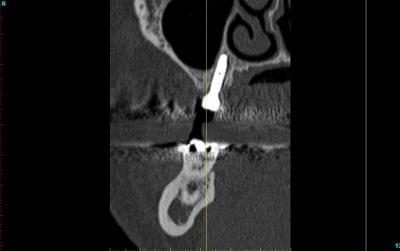

votre système est peut être bien mais ne croyez pas que sans on ne peut rien faire...

d'autant plus que sur une coupe, l'axe n'est pas génial par rapport à la 6....

2 coupes scan pour exemple, de ce que n'importe quel praticien lambda, peut faire à main levé avec un minimum de sensibilité et d'attention. implant posé et l'autre coté va être fait pareil